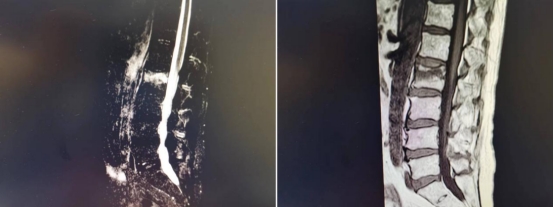

影像学检查示L2腰椎椎体新鲜压缩性骨折

患者来院后行腰椎X线检查,未见明显骨折表现,但考虑到患者腰部剧烈疼痛,且骨质疏松,很有可能发生了骨松性病理性骨折,进一步行腰椎核磁检查,发现患者腰椎压缩性骨折,并伴有轻度腰椎后凸畸形。王岩松教授,程道林主治医师经过详细询问病史、系统体格检查,辅以各项影像学检查,确诊患者为腰椎L2椎体压缩性骨折。王岩松告诉患者家属,传统的治疗方式是通过腰后路开放手术,置入腰椎后路钉棒系统,达到恢复骨折椎体高度,恢复腰椎整体即刻稳定性的目的。但患者90岁高龄,且合并慢性阻塞性肺疾病、肺气肿、冠心病等多种基础疾病。该手术方式需要在全麻下进行,手术创伤相对较大,存在较高风险。若行保守治疗则需要严格卧床至少3个月,但长期卧床会导致患者骨量流失,每卧床一周骨量就会减少1%,而且长期卧床还会导致压疮、坠积性肺炎、尿路感染等严重卧床并发症,对老人的生命造成极大威胁。